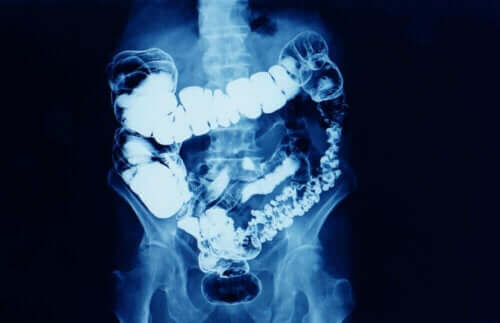

Over het algemeen is constipatie wanneer de frequentie van het passeren van ontlasting afneemt. Constipatie is een symptoom dat betekent dat de darmtransit om de een of andere reden wordt verminderd.